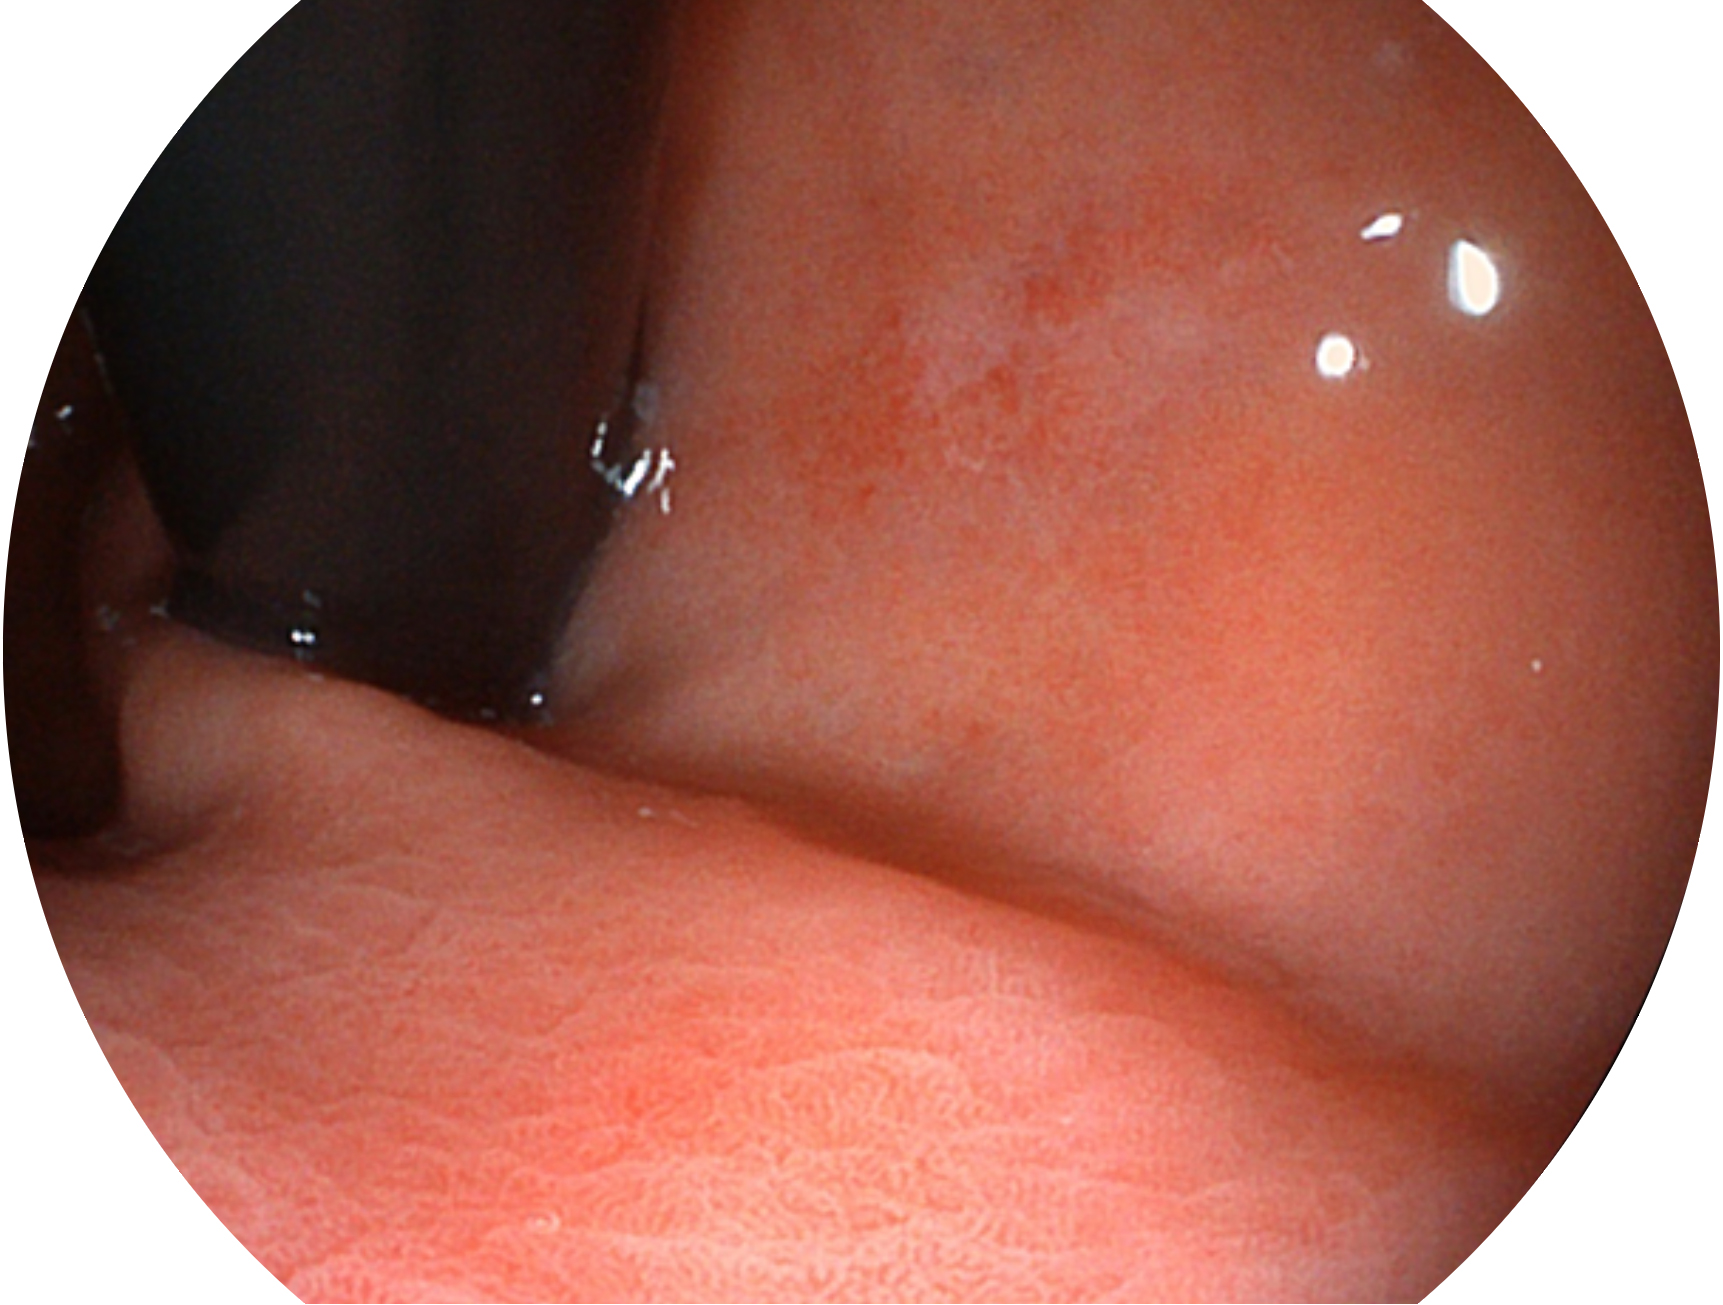

開(kāi)立新開(kāi)發(fā)的內(nèi)鏡染色技術(shù),主要是基于多波長(zhǎng)LED 光源的開(kāi)發(fā),VLS-55Q 四波長(zhǎng)LED 光源是由四個(gè)不同顏色的LED光按照相應(yīng)照明模式所規(guī)定的特定發(fā)光比例進(jìn)行合束后形成,合束后形成的照明光的光譜由紅光、綠光、藍(lán)光及藍(lán)紫光這四個(gè)不同的波段范圍構(gòu)成。具有更高光譜自由度,通過(guò)光譜比例的控制,實(shí)現(xiàn)了聚譜成像技術(shù),英文全稱為“Spectral Focused Imaging, SFI”,縮寫為“SFI”和光電復(fù)合染色成像技術(shù),英文全稱為“Versatile Intelligent Staining Technology, VIST”,縮寫為“VIST”。